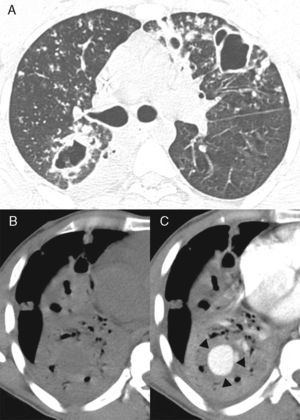

We would like to report a similar case of a 37-year-old man who was admitted to the emergency room with hemoptysis. The patient had a history of pulmonary tuberculosis (TB), treated irregularly for the previous 2 years. Sputum was positive for acid-fast bacilli. Fiberoptic bronchoscopy showed active bleeding from the right lower-lobe bronchus. Contrast-enhanced chest CT revealed nodules and cavities suggestive of active pulmonary TB, and consolidation in the right lower lobe with a rounded enhancing lesion within the consolidated area (Fig. 1). Transcatheter embolization with coils was performed. The patient also received TB therapy and recovered well, with no recurrence of bleeding during 1 year of follow-up.

(A) Axial CT image obtained with the lung window setting at the level of bronchial bifurcation, showing multiple bilateral nodules and cavities in the lung parenchyma. CT images obtained with the mediastinal window setting at the level of the lower lobes before (B) and after (C) contrast administration reveal consolidation in the right lower lobe with a rounded enhancing lesion inside the consolidated area (arrows).